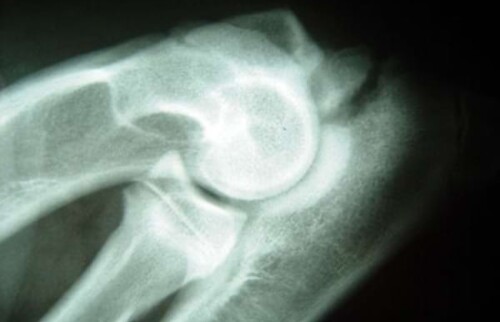

Nach der klinischen Untersuchung sollte zur Diagnosesicherung eine röntgenologische Untersuchung des Ellbogengelenks durchgeführt werden.

Berner Sennenhund, männlich, 6 Monate: Ellbogen in gebeugter Haltung. Der Isolierte Prozessus Anconaeus wird überlagerungsfrei dargestellt.